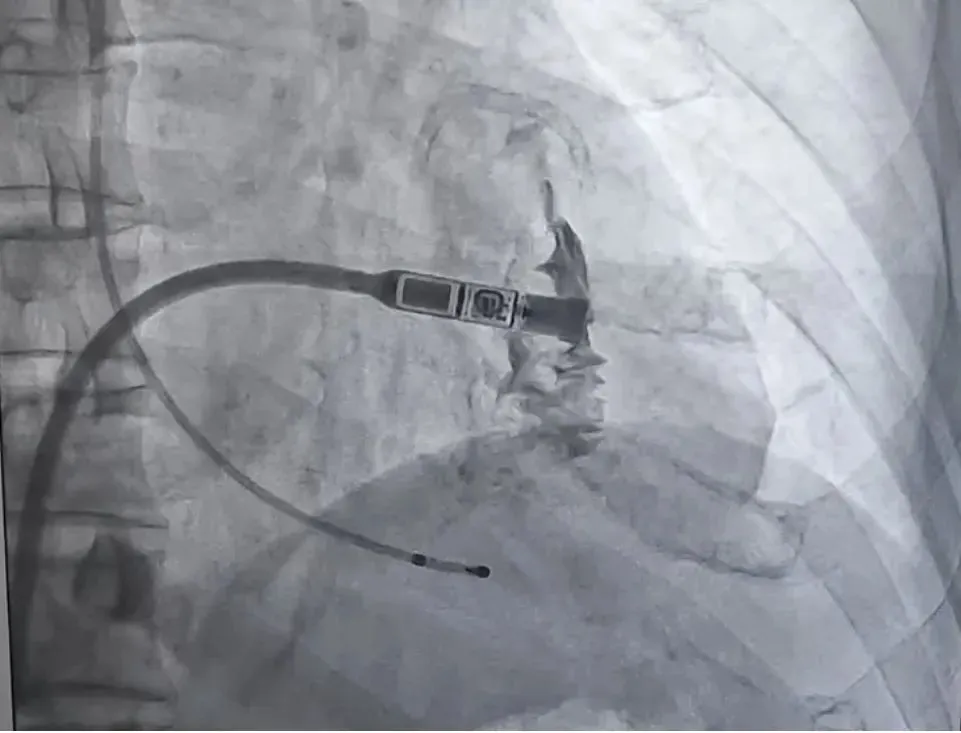

术中,在局部麻醉下,心病科团队通过股静脉穿刺建立通道,送入传送鞘管,在传送鞘管内通过递送系统将Micra无导线起搏器精准输送到右心室间隔部,释放成功后进行电学参数和稳定性测试,均符合要求,手术顺利完成。现患者恢复良好,已平安出院。